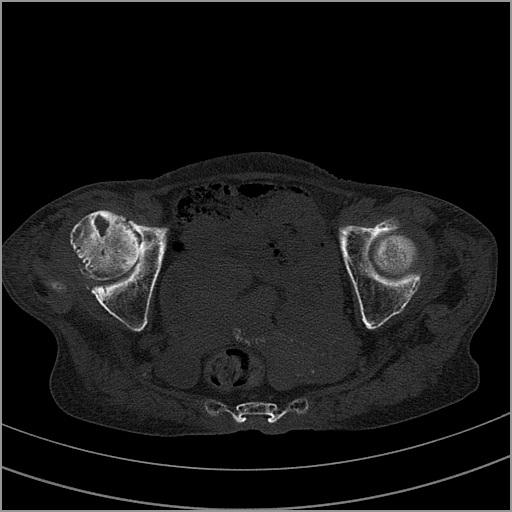

以下是引用老爱克斯新网客在2009-2-3 19:42:00的发言:[br]右侧髋臼及右侧股骨头可见明显骨质破坏,以溶骨性破坏为主,无明显硬化,髋关节间隙变窄,周围软组织明显肿胀,密度不均,脂肪间隙消失。[br] 诊断:右侧髋关节感染性病变,右侧髋关节结核的可能大。[br] 鉴别诊断:1.股骨头缺血坏死,单纯股骨头缺血坏死病例不会累积髋臼骨破坏。2。退行性关节炎,以骨质增生为主,伴有关节面硬化,骨质破坏呈多发小囊状破坏为主,其周围可见硬化环。3.股骨头缺血坏死晚期(第四期)骨质破坏可伴髋关节退行性变,可有骨质增生,但此时骨破坏以股骨头破坏为主,不应该伴有髋臼骨质破坏,因为股骨头的骨破坏是因血运中断,而没有髋臼的血运中断,又没有细菌的感染,怎么能造成髋臼的骨破坏呢。